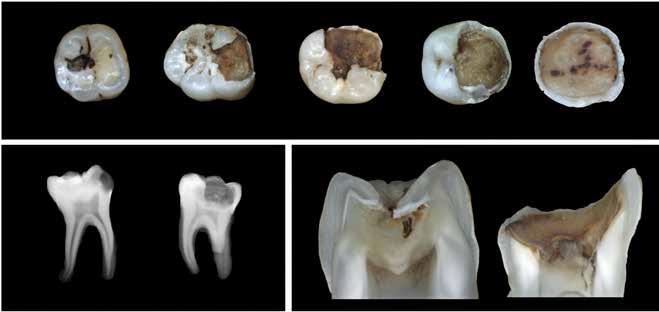

Fig. 4. Histologiske eksempler på ektopisk bindevævsdannelse (brusk). Ektopisk bindevæv er synligt radiografisk (A) såvel som makroskopisk (B). Det ektopiske bindevæv har brusklignende celler arrangeret i lakuner (C). Farvning med Safranin O (D), Alcian Blue van Gieson (E) og Toluidin blå (F) bekræftede tilstedeværelsen af en glycosaminoglycan-rig matrix. (Med tilladelse fra (29)).

Fig. 4. Histological examples of ectopic connective tissue formation (cartilage). Ectopic connective tissue is visible radiographically (A) as well as macroscopically (B). The ectopic connective tissue appears cartilage-like with cells arranged in lacunae (C). Staining with Safranin O (D), Alcian blue van Gieson (E) and Toluidine Blue (F) confirmed the presence of a glycosaminoglycan rich matrix. (With permission from (29)).

ØVRIGE BASALBIOLOGISKE FUND

VED EKSTENSIV CARIES

I en nylig forsvaret ph.d.-afhandling blev der gjort nogle basalbiologiske opsigtsvækkende fund ved en nærmere undersøgelse af ubehandlede ekstremt dybe carieslæsioner (29). I et stort antal af de undersøgte carieslæsioner sås brusklignende forandringer i det pulpale stroma direkte under carieslæsionen. Disse bruskagtige dannelser var distinkt anderledes end klassiske pulpasten og var signifikant associeret med inflammation i pulpa samt med øget intrapulpal mineralisering vurderet radiologisk (Fig. 4). Studiet fremsatte den hypotese, at det måske ville være muligt at benytte forekomsten af radiologisk synlig intrapulpal mineralisering som en noninvasiv indikator for pulpal skade. I studiet sås desuden en høj forekomst af pulpapolypper, hvilket viser, at det inflammerede pulpale væv har tendens til at undergå hyperplastiske forandringer (Fig. 5).